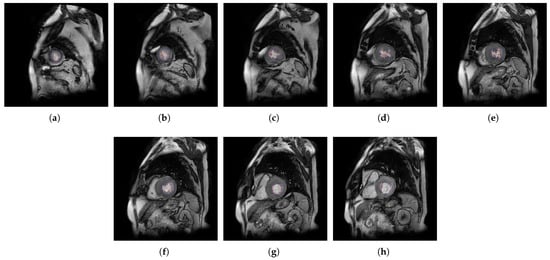

2. Methods

2.1. A Software Tool to Quantify the Trabeculae Degree in the LV Myocardium for a Population of Patients with Genetic Cardiomyopathies (QLVTHCI)

- The different MSERs are detected in a centered ROI of each input image by the use of OpenCV [23]. As the LV cavity is normally represented by a circular shape, the centroid of each MSER detected is computed in order to automatically identify the left ventricle cavity anywhere in the image and for applying the convex hull.

- The previous application of the convex hull allows a second refining to optimize the search process of the external layer and the trabeculae areas. The parameter e-expand is redefined and adjusted to accurately determine the external layer of the compact zone, thanks to plotting several lines from the centroid of the LV to reach the points of the external layer. This parameter establishes the distance of the lines between the centroid of the LV cavity and the possible space where the external layer can be found, taking into account the particular features of genetic cardiomyopathies. We optimized the parameter e-expand for different situations or possible cardiomyopathies.

2.4. Populations

- A set of 59 patients (identified from X1 to X59) with previously diagnosed cardiomyopathies such as non-compacted cardiomyopathy, RV or LV arrhythmogenic cardiomyopathy, DCM, HCM, unclassifiable or mixed cardiomyopathies, and inherited cardiomyopathies.

- A group of 27 patients (identified as P1 to P27) with previously diagnosed LVNC cardiomyopathy meeting Petersen’s criteria [14].